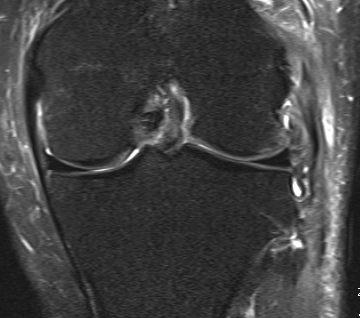

MRI

Chronic distal avulsion LCL

Sagittal MRI showing torn ACL Coronal MRI demonstrating chronic avulsion LCL fibula head